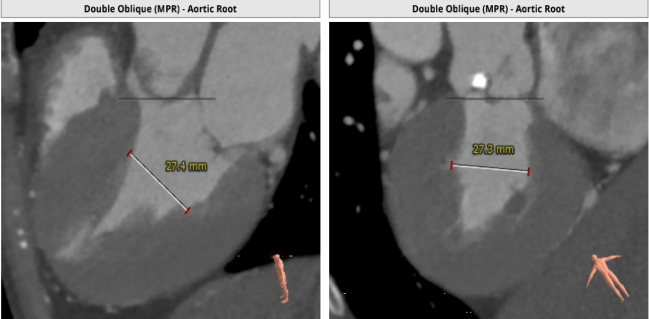

主动脉根部解剖CT影像

TYPE 0型主动脉瓣,瓣环径22mm,瓣上结构分析仅有左侧窦单瓣叶钙化,右侧窦瓣叶柔软无支撑。应用downsize策略(23mm瓣膜)不排除会出现瓣膜固定不稳,飞瓣或下滑可能。

左侧窦瓣叶钙化,左侧窦平且冠脉高度不足,右侧窦也不大,且预计瓣叶长度高于右冠高度,双侧冠脉均有遮挡风险。